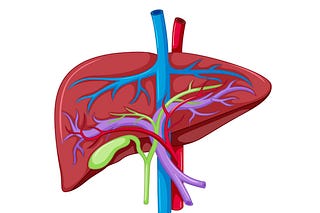

Empleo de telmisartán en perros con hipertensión portal

Revisa todas las diapositivas de este interesante estudio clínico.

Empleo de telmisartán en perros con hipertensión portal hepática (II)

Estudio sobre el empleo de telmisartán en hipertensión portal en perros con enfermedad hepática

Empleo de telmisartán en perros con hipertensión portal hepática (I)